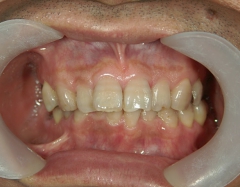

矯正歯科 治療後矯正歯科 全顎ワイヤー矯正 治療後矯正歯科(全顎ワイヤー矯正)治療後

矯正歯科 治療後 左上6番欠損のため、7番を6番の位置へ前方牽引

no.22_8175_治療後_右.jpgno.22_8175_治療後_正面.jpgno.22_8175_治療後_左.jpg